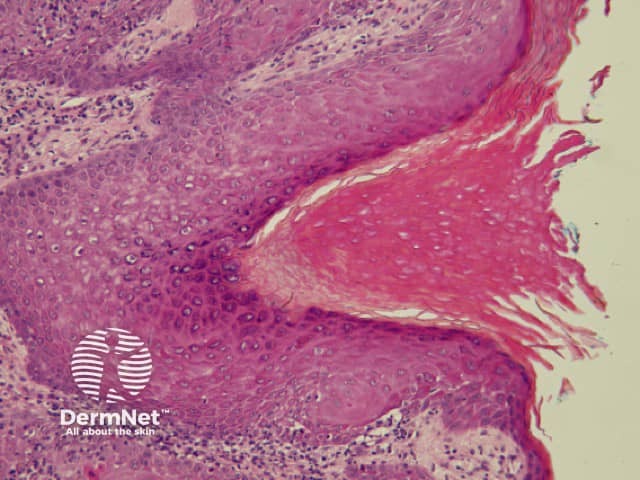

Seborrhoeic keratoses are amongst the most variable lesions on dermatoscopy, which is reflected in their protean histological appearances (Figure 15). Aside from the pseudopod pattern, any pattern or colour can be found. Flat seborrhoeic keratoses appear similar to solar lentigo on dermatoscopy. With early epidermal acanthosis thin curved lines (Figure 13) and circles become manifest, whilst with advanced acanthosis thick curved lines (Figure 14) and clods typically predominate. White clods are due to keratin under the stratum corneum. Orthokeratotic loosely laminated surface keratin appears yellow. Crypts fill with discoloured keratin and may appear various colours on dermatoscopy including brown and orange (Figure 15).

Figure 13 Figure 14 Figure 15

Figure 15a Figure 15b Figure 15c